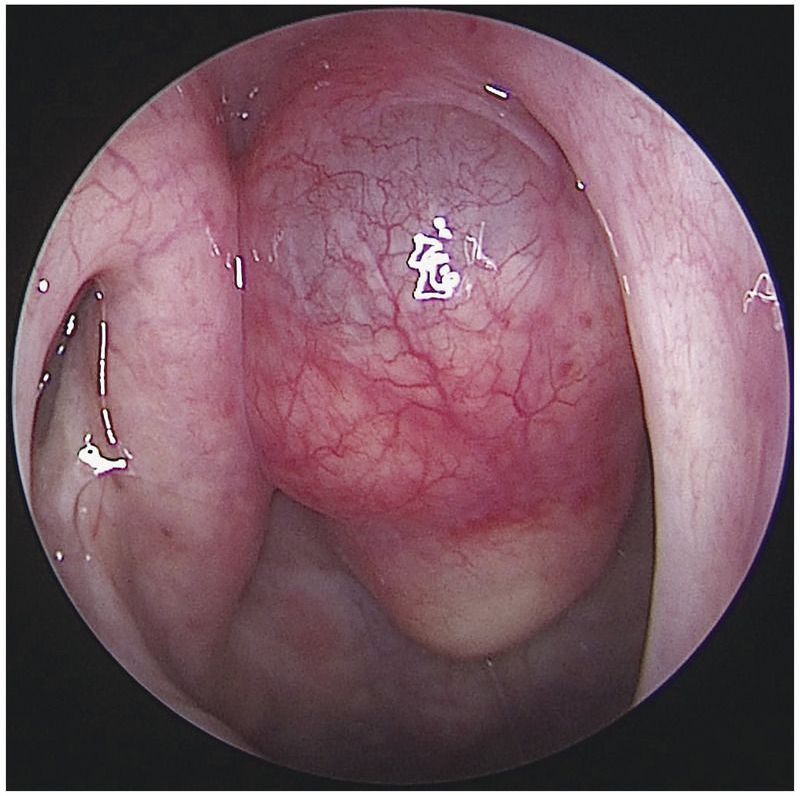

A 60-year-old man presented to the otorhinolaryngology clinic with a feeling of nasal obstruction and postnasal drip that had developed 10 years earlier and had worsened over the past month. He also had a sensation of a foreign body in his throat. Symptoms worsened when he was lying flat. On physical examination, no deviation of the nasal septum or hypertrophy of the inferior turbinates was detected. Nasopharyngoscopy revealed a smooth, pink, cystic mass in the midline of his nasopharynx, with no obstruction of the openings to the eustachian tubes (the image shows the view through the right naris). Computed tomography of the head revealed a 2.5 cm by 1.3 cm by 1.4 cm cystic tumor in the midline of the nasopharynx without intracranial extension. The findings were consistent with Tornwaldt’s cyst, a benign cyst that arises between the roof of the nasopharynx and the remnant of the notochord. Because the patient was symptomatic, he underwent surgical marsupialization of the cyst. On follow-up examination 3 months after surgery, he no longer had the sensation of a foreign body in his throat, his nasal symptoms were reduced, and there was no recurrence of the cyst.